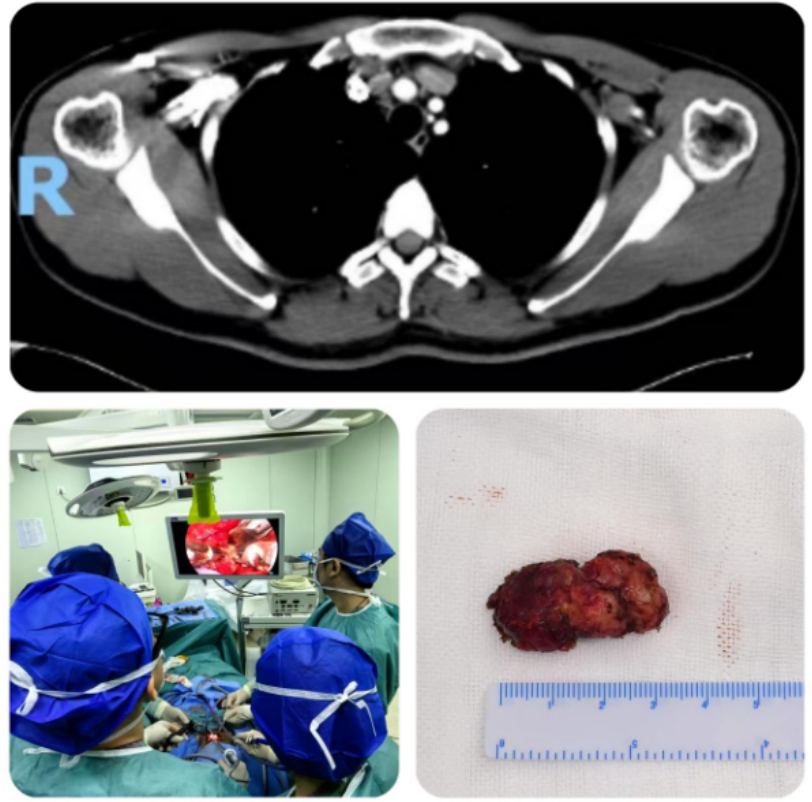

患者为36岁青年男性,术前甲状腺彩超提示:甲状腺右叶结节为2.2x1.5x1.2cm(TI-RADS 5类),增强CT提示:右侧颈部、气管前方、纵隔内多发肿大淋巴结,FNA示:(右叶)甲状腺髓样癌,(气管周围淋巴结)查见癌细胞,(右颈部淋巴结)查见癌细胞。在传统治疗方案中,上纵隔淋巴结清扫多需联合开胸或胸腔镜手术,不仅手术创伤大、术后恢复时间长,还可能引发肺部感染、胸廓畸形等并发症,给患者带来额外负担。面对这一治疗难题,盛蕾副主任医师充分评估患者病情,与曾庆东教授、吕斌教授反复研讨手术方案后,决定突破传统入路限制,创新性采用经颈部切口入路腔镜辅助上纵隔淋巴结清扫术。

术中探查见患者甲状腺右侧II,III,IV区及上纵隔淋巴结肿大,部分融合成团,大者约3cm,自颈内静脉向外侧剥离淋巴结,于锁骨上方水平向深面切开脂肪组织至前、中、后斜角肌及肩胛提肌表面,并沿上述肌肉表面向上游离,于二腹肌后腹下方行腔镜辅助右颈部功能性淋巴结清扫,术中显露并保护舌下神经、膈神经、臂丛神经、颈横血、副神经。继续行上纵隔淋巴结清扫术,钝性游离胸腺,显露无名动脉。打开血管鞘膜,腔镜下分离无名动脉下方、右侧无名静脉与主动脉弓上方的2R区淋巴结,将肿大淋巴结完整切除,术中注意保护迷走神经、喉返神经、淋巴管、右胸膜及主动脉弓等重要脏器。

该手术全程避免传统开胸操作,在精准清除转移淋巴结的同时,最大限度降低手术创伤,为甲状腺癌合并纵隔转移患者提供了更优的微创治疗选择。在麻醉科医师的精准护航与手术室护理团队的高效协作下,整台手术过程顺利,手术仅历时3小时,颈部切口6cm,术中出血量约30毫升。患者术后安返病房,在甲状腺外科护理团队实施的加速康复理念指导下,患者得到了精准化、个性化护理,患者于术后第四日顺利出院,生动诠释了“微创”与“快速康复”的完美结合。